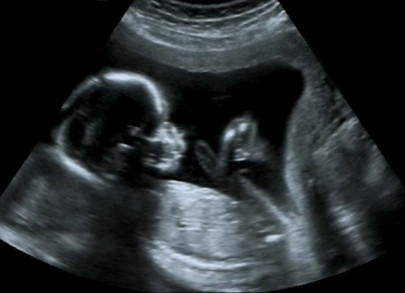

Basic health centres: CM orders 24-hour ultrasound service

CM gives approval to purchase ultrasound machines for basic health centres across the province.